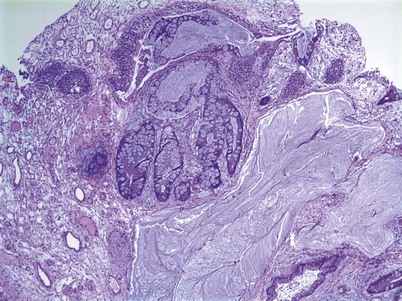

An inverted papilloma is a benign proliferative lesion that is associated with chronic inflammation or bladder outlet obstruction and can be located throughout the bladder but most commonly on the trigone, comprising less than 1% of all bladder tumors (Sung et al, 2006; Jones et al, 2007; Kilciler et al, 2008). Inverted papillomas demonstrate an inverted growth pattern composed of anastomosing islands of histologically and cytologically normal urothelial cells invaginating from the surface urothelium into the lamina propria but not into the muscularis propria (Fig. 80–1) (Sung et al, 2006). When diagnosed according to strictly defined criteria (e.g., lack of cytologic atypia), inverted papillomas behave in a benign fashion with only a 1% incidence of tumor recurrence (Sung et al, 2006; Kilciler et al, 2008). Occasionally, inverted papillomas are present with coexistent urothelial cancer elsewhere in the urinary system, occurring more commonly in the upper tract than the bladder (Asano et al, 2003). The use of fluorescent in-situ hybridization (FISH) to evaluate chromosomal changes can distinguish between an inverted papilloma and a urothelial cancer with an inverted growth pattern (Jones et al, 2007). Transurethral resection is the treatment of choice.